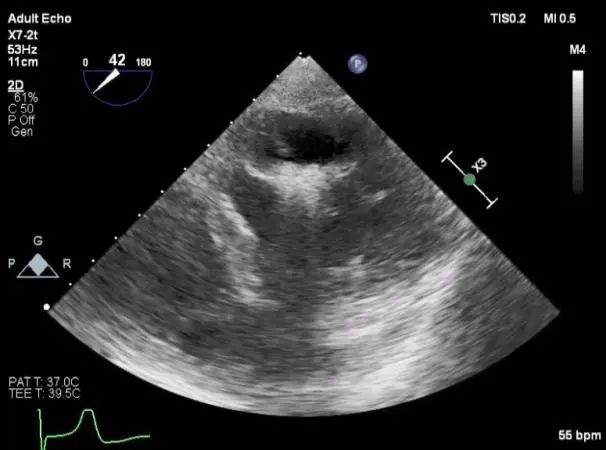

麻醉状态下TEE显示中大量返流MR:

房间隔穿刺:

Bicaval 寻找穿刺点

穿刺点距离二尖瓣环3.42cm